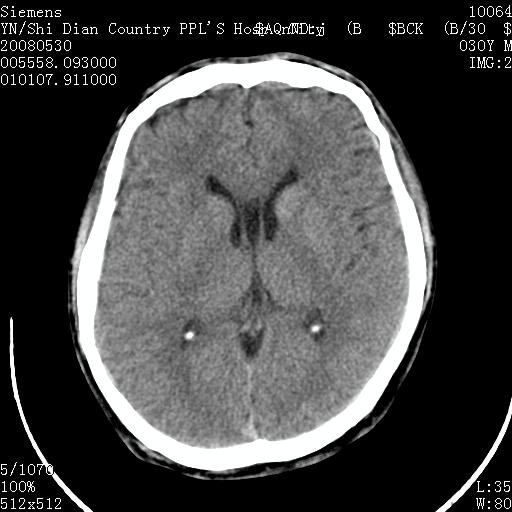

以下是引用pujunzhi在2008-7-10 13:06:00的发言:[br]透明间隔腔

以下是引用随光逐影在2008-7-10 15:19:00的发言:[br]1)考虑左侧尾状核钙化。2)透间隔间腔与vergae腔并存。

以下是引用卜一在2008-7-10 16:43:00的发言:[br]1)考虑左侧尾状核钙化。2)透间隔间腔形成。支持!